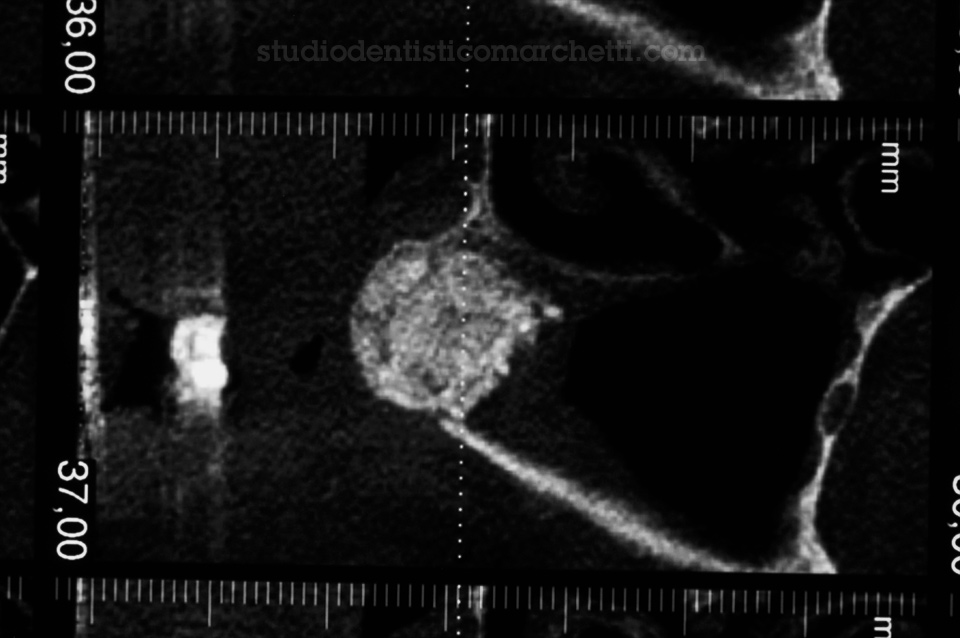

Chirurgia Orale

Estrazione di Dente del Giudizio Incluso

Chirurgia Orale

Estrazione di Dente del Giudizio Incluso

Chirurgia Orale

Estrazione di Dente del Giudizio Incluso